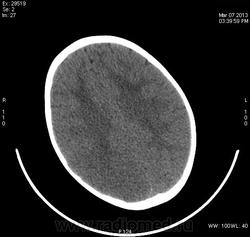

Предположу снижение плотности в правой лобно-теменно-височной области - инсульт в бассейне правой СМА?

Теменная, затылочная справа, ишемический инсульт. С бассейна СМА, как мне видится, "залезает" на бассейн ЗМА, - возможно, вариант развития виллизиева круга.